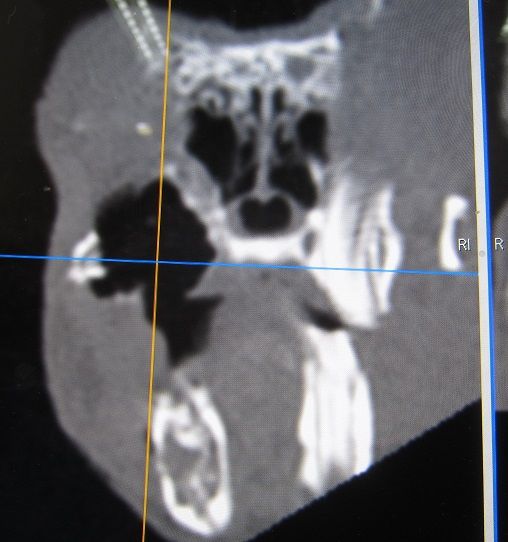

途中経過をCTで

まだまだたくさん残ってますが、👆これが👇こうなります。